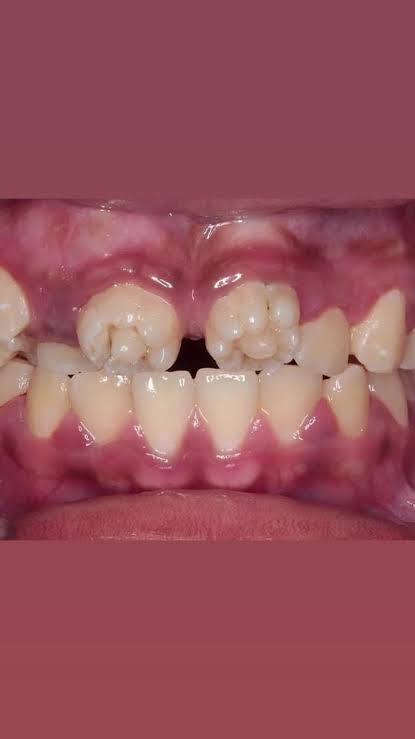

梅毒なんてまだあるのか…

ギザ歯の子って梅毒なんだ…

まず先天的にこの形になる事があるのを今知った

ちょっとヘラった人がやる人体改造の一種とばかり

ハッチンソン歯でググったけどこんな綺麗に全部ギザ歯になる?ってなった

>ちょっとヘラった人がやる人体改造の一種とばかり

先天性梅毒なせいでヘラったと考えられる

>母体から感染するって事…?

もちろんそうだ

妊娠中に梅毒に感染して子供に伝染るのが先天梅毒

基本的に抗生剤で治せる大人の梅毒とは話が違う

>ギザ歯の子って梅毒なんだ…

先天梅毒だとギザ歯になるが

ギザ歯だからと言って先天梅毒とは限らない

>そのはずなのでスレ画はなんか違うんじゃねえかなって言われたりしてるね

円錐歯は外胚葉性異形成症にも見られるからはっきりとしない

こういう歯の形態異常に関する問題は国試終わったばっかの歯学部生が一番知ってると思う

昨日のスレでハッチンソンも梅毒も関係ないってバラされてたのにまた建てたの?